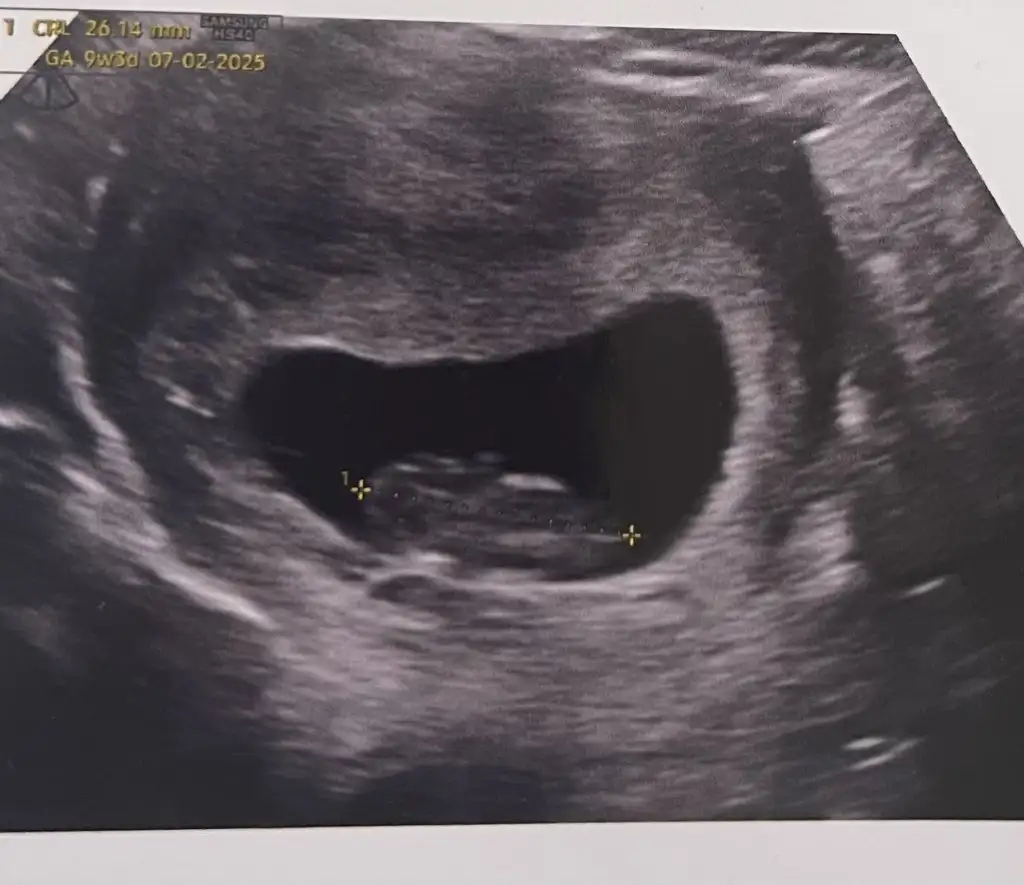

Benimkinde bi tahminde bulunurmusunjz 9+5 karından ultrasonSizin beybi de küçük:)

ErkekBenimkinde bi tahminde bulunurmusunjz 9+5 karından ultrason